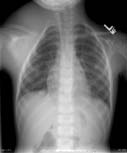

Chest x-ray. Frontal view of a male patient.